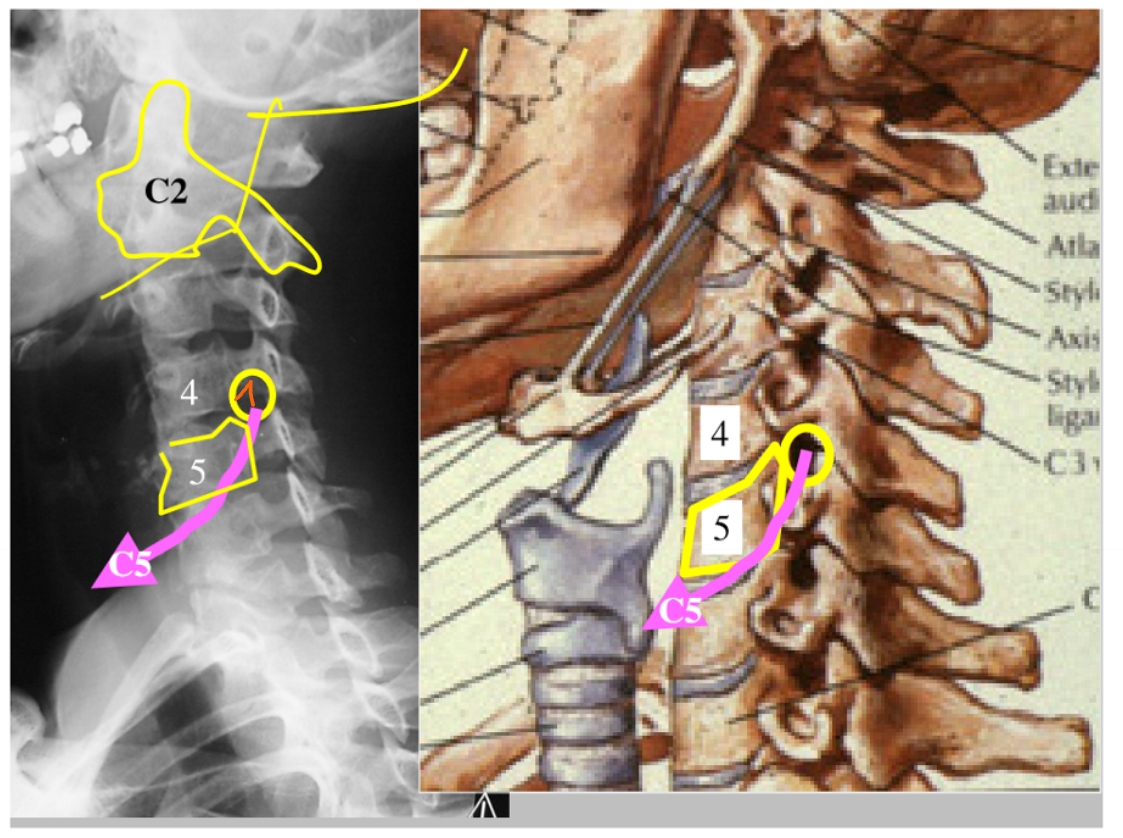

arcus anterior

arcus posterior

dens axis

processus uncinatus

corpus C4

processus uncinatus

processus spinosus C6

processus spinosus C7

corpus T1

processus transversus T1

→ T1: beste referentie => heeft grote processi transversi

arcus anterior C1

→ articulatio atlanto-axialisch-mediana = gewricht (daarrond roteren we ons hoofd)

dens axis

arcus posterior C1

processus spinosus C2

corpus C4

corpus C6

processus spinosus C7

processus articularis superior C6 & processus articularis inferior C6 → facetgewricht

processus spinosus C6

pedikel

= klein beenbrugje

ramus mandibulae

angulus mandibulae

corpus mandibulae

formamina intervertebrale

hier komen de spinale zenuwen uit

(linker beeld → linkerkaak)

schuine opname = oblique view

foramen intervertebrale C4-C5 (links)

daaruit komt spinale zenuw C5

processus uncinatus (linker)

pedikel (linker)